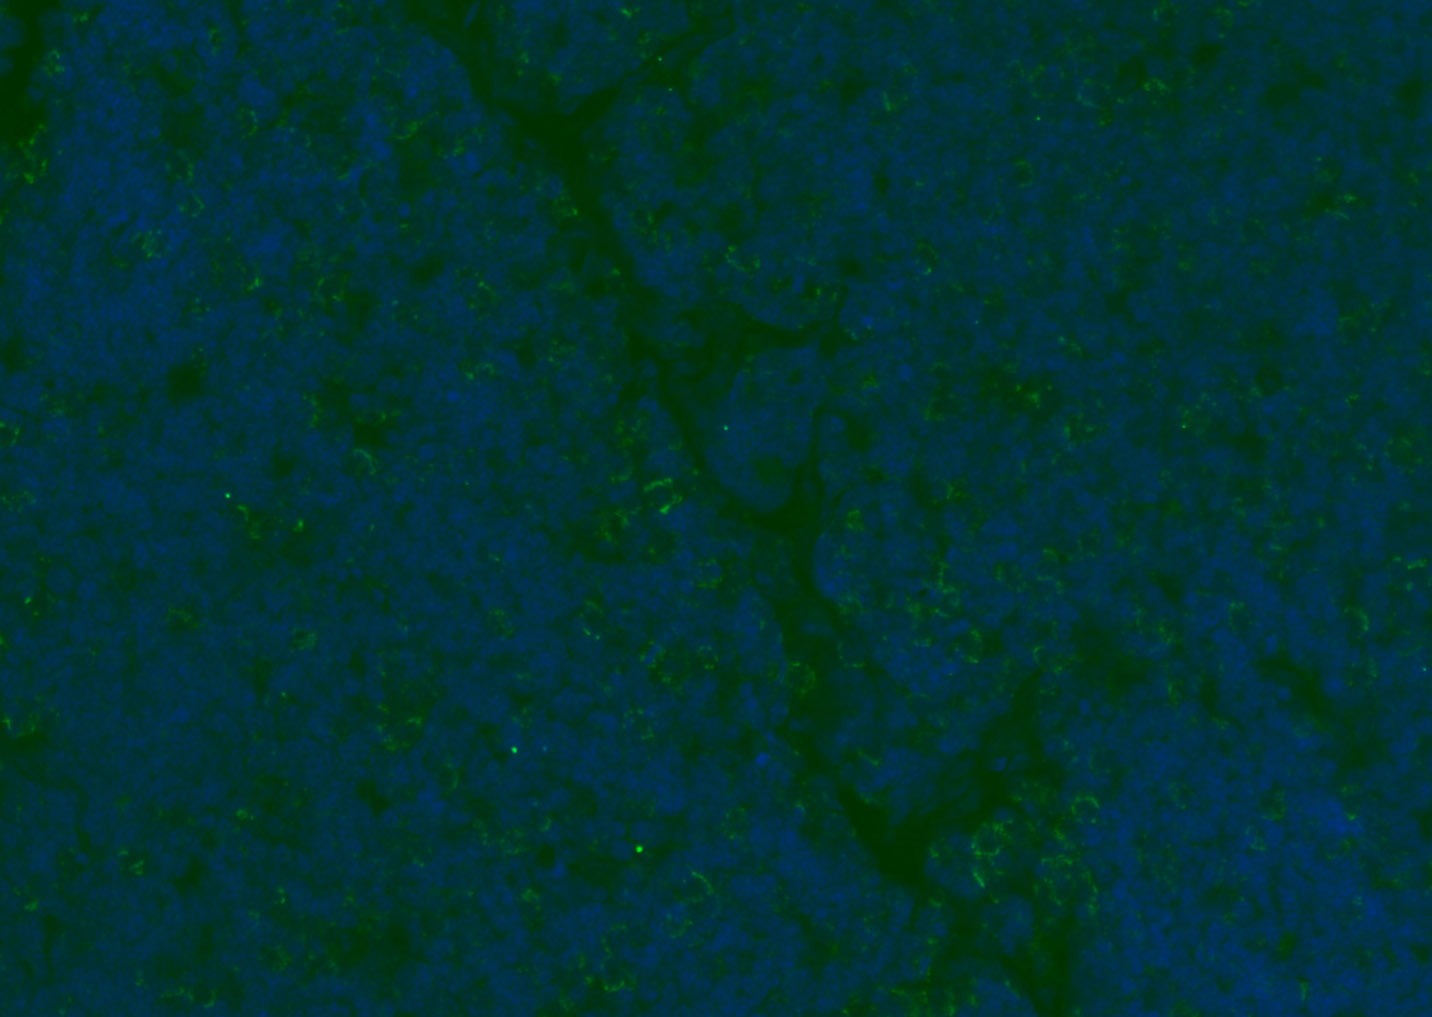

| Verified Activity | 1. Tissue/cell: human lung carcinoma;4% Paraformaldehyde-fixed and paraffin-embedded; Antigen retrieval: citrate buffer (0.01M, pH6.0), Boiling bathing for 15 min; Blocking buffer (normal goat serum) at 37°C for 20 min; Incubation: Anti-CD8 Polyclonal Antibody, Unconjugated (TMAB-00392) 1:200, overnight at 4°C; The secondary antibody was Goat Anti-Rabbit IgG, Cy3 conjugated used at 1:200 dilution for 40 minutes at 37°C. DAPI (5 μg/ml,blue) was used to stain the cell nucleus. 2. Paraformaldehyde-fixed, paraffin embedded (mouse lymphoid); Antigen retrieval by boiling in sodium citrate buffer (pH6.0) for 15 min; Blocking buffer (normal goat serum) at 37°C for 30 min; Antibody incubation with (CD8B) Polyclonal Antibody, Unconjugated (TMAB-00392) at 1:200 overnight at 4°C, followed by a conjugated Goat Anti-Rabbit IgG antibody for 90 minutes, and DAPI for nucleus staining. 3. Paraformaldehyde-fixed, paraffin embedded (rat spleen); Antigen retrieval by boiling in sodium citrate buffer (pH6.0) for 15 min; Blocking buffer (normal goat serum) at 37°C for 30 min; Antibody incubation with (CD8B) Polyclonal Antibody, Unconjugated (TMAB-00392) at 1:200 overnight at 4°C, followed by a conjugated Goat Anti-Rabbit IgG antibody for 90 minutes, and DAPI for nucleus staining. 4. Paraformaldehyde-fixed, paraffin embedded (mouse thymus); Antigen retrieval by boiling in sodium citrate buffer (pH6.0) for 15 min; Blocking buffer (normal goat serum) at 37°C for 30 min; Antibody incubation with (CD8B) Polyclonal Antibody, Unconjugated (TMAB-00392) at 1:200 overnight at 4°C, followed by a conjugated Goat Anti-Rabbit IgG antibody for 90 minutes, and DAPI for nucleus staining. 5. Paraformaldehyde-fixed, paraffin embedded (rat lymphoid); Antigen retrieval by boiling in sodium citrate buffer (pH6.0) for 15 min; Blocking buffer (normal goat serum) at 37°C for 30 min; Antibody incubation with (CD8B) Polyclonal Antibody, Unconjugated (TMAB-00392) at 1:200 overnight at 4°C, followed by a conjugated Goat Anti-Rabbit IgG antibody for 90 minutes, and DAPI for nucleus staining. 6. Paraformaldehyde-fixed, paraffin embedded (rat thymus); Antigen retrieval by boiling in sodium citrate buffer (pH6.0) for 15 min; Blocking buffer (normal goat serum) at 37°C for 30 min; Antibody incubation with (CD8B) Polyclonal Antibody, Unconjugated (TMAB-00392) at 1:200 overnight at 4°C, followed by a conjugated Goat Anti-Rabbit IgG antibody for 90 minutes, and DAPI for nucleus staining. 7. Paraformaldehyde-fixed, paraffin embedded (human tonsil); Antigen retrieval by boiling in sodium citrate buffer (pH6.0) for 15 min; Blocking buffer (normal goat serum) at 37°C for 30 min; Antibody incubation with (CD8B) Polyclonal Antibody, Unconjugated (TMAB-00392) at 1:200 overnight at 4°C, followed by a conjugated Goat Anti-Rabbit IgG antibody for 90 minutes, and DAPI for nucleus staining. 8. Paraformaldehyde-fixed, paraffin embedded (mouse lymphoid); Antigen retrieval by boiling in sodium citrate buffer (pH6.0) for 15 min; Blocking buffer (normal goat serum) at 37°C for 30 min; Antibody incubation with (CD8B) Polyclonal Antibody, Unconjugated (TMAB-00392) at 1:200 overnight at 4°C, followed by a conjugated Goat Anti-Rabbit IgG antibody for 90 minutes, and DAPI for nucleus staining. 9. Paraformaldehyde-fixed, paraffin embedded (rat thymus); Antigen retrieval by boiling in sodium citrate buffer (pH6.0) for 15 min; Blocking buffer (normal goat serum) at 37°C for 30 min; Antibody incubation with (CD8B) Polyclonal Antibody, Unconjugated (TMAB-00392) at 1:200 overnight at 4°C, followed by a conjugated Goat Anti-Rabbit IgG antibody for 90 minutes, and DAPI for nucleus staining. 10. Paraformaldehyde-fixed, paraffin embedded (human tonsil); Antigen retrieval by boiling in sodium citrate buffer (pH6.0) for 15 min; Blocking buffer (normal goat serum) at 37°C for 30 min; Antibody incubation with (CD8B) Polyclonal Antibody, Unconjugated (TMAB-00392) at 1:200 overnight at 4°C, followed by a conjugated Goat Anti-Rabbit IgG antibody for 90 minutes, and DAPI for nucleus staining. 11. Paraformaldehyde-fixed, paraffin embedded (mouse spleen); Antigen retrieval by boiling in sodium citrate buffer (pH6.0) for 15 min; Blocking buffer (normal goat serum) at 37°C for 30 min; Antibody incubation with (CD8B) Polyclonal Antibody, Unconjugated (TMAB-00392) at 1:200 overnight at 4°C, followed by a conjugated Goat Anti-Rabbit IgG antibody for 90 minutes, and DAPI for nucleus staining. 12. Paraformaldehyde-fixed, paraffin embedded (rat lymphoid); Antigen retrieval by boiling in sodium citrate buffer (pH6.0) for 15 min; Blocking buffer (normal goat serum) at 37°C for 30 min; Antibody incubation with (CD8B) Polyclonal Antibody, Unconjugated (TMAB-00392) at 1:200 overnight at 4°C, followed by a conjugated Goat Anti-Rabbit IgG antibody for 90 minutes, and DAPI for nucleus staining. 13. Paraformaldehyde-fixed, paraffin embedded (Rat lymphoid); Antigen retrieval by boiling in sodium citrate buffer (pH6.0) for 15 min; Blocking buffer (normal goat serum) at 37°C for 30 min; Antibody incubation with (CD8B) Polyclonal Antibody, Unconjugated (TMAB-00392) at 1:100 overnight at 4°C, followed by a conjugated Goat Anti-Rabbit IgG antibody for 90 minutes, and DAPI for nucleus staining. 14. Paraformaldehyde-fixed, paraffin embedded (mouse thymus); Antigen retrieval by boiling in sodium citrate buffer (pH6.0) for 15 min; Blocking buffer (normal goat serum) at 37°C for 30 min; Antibody incubation with (CD8B) Polyclonal Antibody, Unconjugated (TMAB-00392) at 1:100 overnight at 4°C, followed by a conjugated Goat Anti-Rabbit IgG antibody for 90 minutes, and DAPI for nucleus staining. 15. Paraformaldehyde-fixed, paraffin embedded (mouse spleen); Antigen retrieval by boiling in sodium citrate buffer (pH6.0) for 15 min; Blocking buffer (normal goat serum) at 37°C for 30 min; Antibody incubation with (CD8B) Polyclonal Antibody, Unconjugated (TMAB-00392) at 1:100 overnight at 4°C, followed by a conjugated Goat Anti-Rabbit IgG antibody for 90 minutes, and DAPI for nucleus staining. 16. Paraformaldehyde-fixed, paraffin embedded (rat spleen); Antigen retrieval by boiling in sodium citrate buffer (pH6.0) for 15 min; Blocking buffer (normal goat serum) at 37°C for 30 min; Antibody incubation with (CD8B) Polyclonal Antibody, Unconjugated (TMAB-00392) at 1:100 overnight at 4°C, followed by a conjugated Goat Anti-Rabbit IgG antibody for 90 minutes, and DAPI for nucleus staining. 17. Paraformaldehyde-fixed, paraffin embedded (rat thymus); Antigen retrieval by boiling in sodium citrate buffer (pH6.0) for 15 min; Blocking buffer (normal goat serum) at 37°C for 30 min; Antibody incubation with (CD8B) Polyclonal Antibody, Unconjugated (TMAB-00392) at 1:100 overnight at 4°C, followed by a conjugated Goat Anti-Rabbit IgG antibody for 90 minutes, and DAPI for nucleus staining. 18. Paraformaldehyde-fixed, paraffin embedded (human tonsil); Antigen retrieval by boiling in sodium citrate buffer (pH6.0) for 15 min; Blocking buffer (normal goat serum) at 37°C for 30 min; Antibody incubation with (CD8B) Polyclonal Antibody, Unconjugated (TMAB-00392) at 1:100 overnight at 4°C, followed by a conjugated Goat Anti-Rabbit IgG antibody for 90 minutes, and DAPI for nucleus staining. 19. Paraformaldehyde-fixed, paraffin embedded (mouse lymphoid); Antigen retrieval by boiling in sodium citrate buffer (pH6.0) for 15 min; Blocking buffer (normal goat serum) at 37°C for 30 min; Antibody incubation with (CD8B) Polyclonal Antibody, Unconjugated (TMAB-00392) at 1:100 overnight at 4°C, followed by a conjugated Goat Anti-Rabbit IgG antibody for 90 minutes, and DAPI for nucleus staining. ![]() ![]() ![]() ![]() ![]() ![]() ![]() ![]() ![]() ![]() ![]() ![]() ![]() ![]() ![]() ![]() ![]() ![]() ![]() |